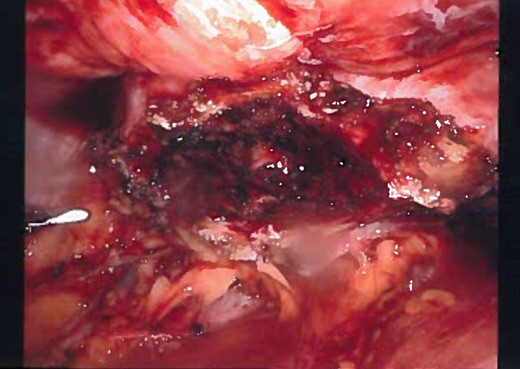

Gross appearance of the urachal cyst resembled an inflammatory and necrotic appearance with multiple cystic cavities (Figs 3 and 7). On pathology, tentative diagnosis of the specimen was confirmed as an urachal cyst. The appearance of an ulcerated cyst wall noted with marked fibrosis, acute and chronic inflammation with focal abscess, foreign body giant cells, and fibrous adhesions, consistent with history of infected urachal cyst and no evidence of malignancy. Intra-operative culture of urachal cyst provided contents positive for Escherichia coli, and negative for fungal material. The patient had an uneventful post-operative course. We followed up the patient in 2 weeks and again in 3 months in the outpatient clinic. During the follow-up, patient reported that removal of the cyst helped her abdominal pain, urinary tract symptoms have completely resolved and constipation was improve pertinently.

Laparoscopic view of the complete dissection of the cyst before removing the port.